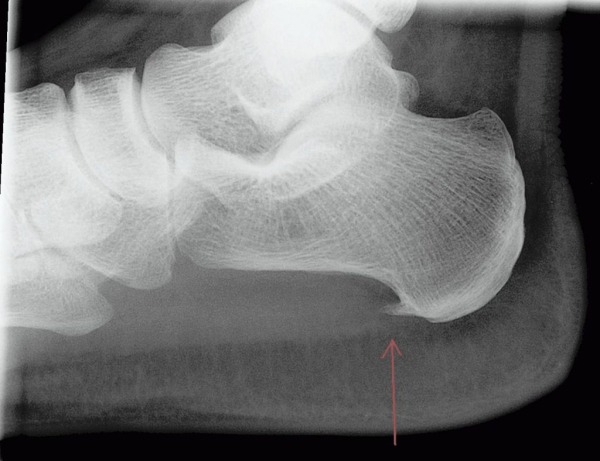

Пяточная шпора

Патология встречается у 80% женщин, большинство из которых живут в городах. Особенность болезни в формировании на пяточной кости острого нароста. Размер шпоры достигает 12 мм, его острая вершина направлена вперед и несколько загибается. Так как образование сдавливает мягкие ткани, костный нарост провоцирует сильную боль и развитие воспаления. Пяточная шпора ― проявление имеющейся в организме патологии.

- Рентген. Позволяет определить наличие костного образования.